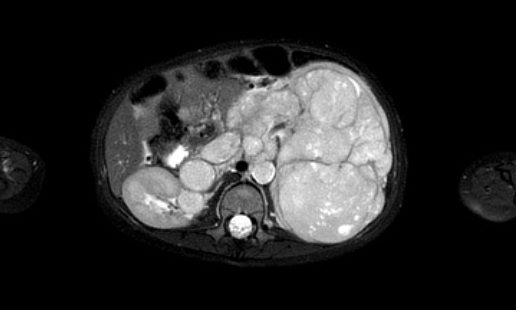

MRI có thể hiển thị rõ ràng huyết khối u trong tĩnh mạch thận và tĩnh mạch chủ dưới, cũng như tình trạng hạch bạch huyết to. Phương pháp này cho phép đo lường khối u một cách chính xác và có thể lặp lại trong các lần khám ban đầu và theo dõi.

Ví dụ 1

Một bé gái ba tuổi có khối u thận trái và huyết khối khối u lớn trong tĩnh mạch thận và tĩnh mạch chủ dưới. Có di căn gan (phát hiện không thường gặp) và di căn phổi.

Lưu ý huyết khối u trong tĩnh mạch thận trái kéo dài vào tĩnh mạch chủ dưới.